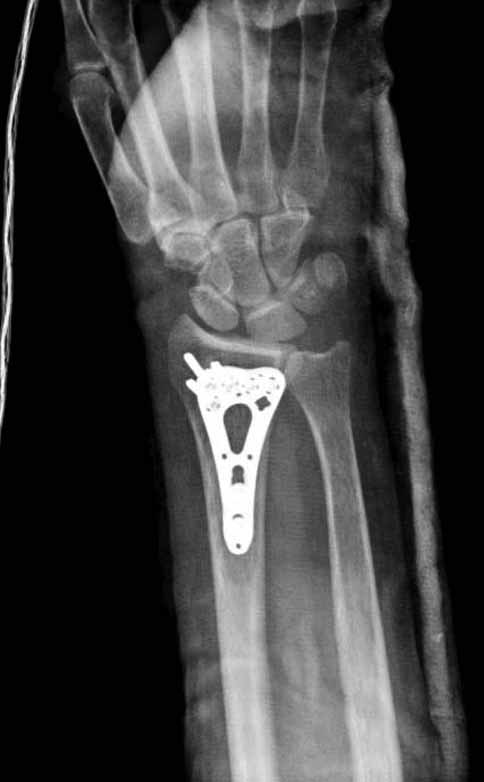

Сегодня все компании: Synthes, Stryker, Zimmer, Acumed, TriMed и т.д. имеют пластины для фиксации дистального перелома лучевой кости. На снимке метод фиксации дистальных переломов, справа Stryker, а слева пластина Synthes,

женщина 58 лет, политравма.